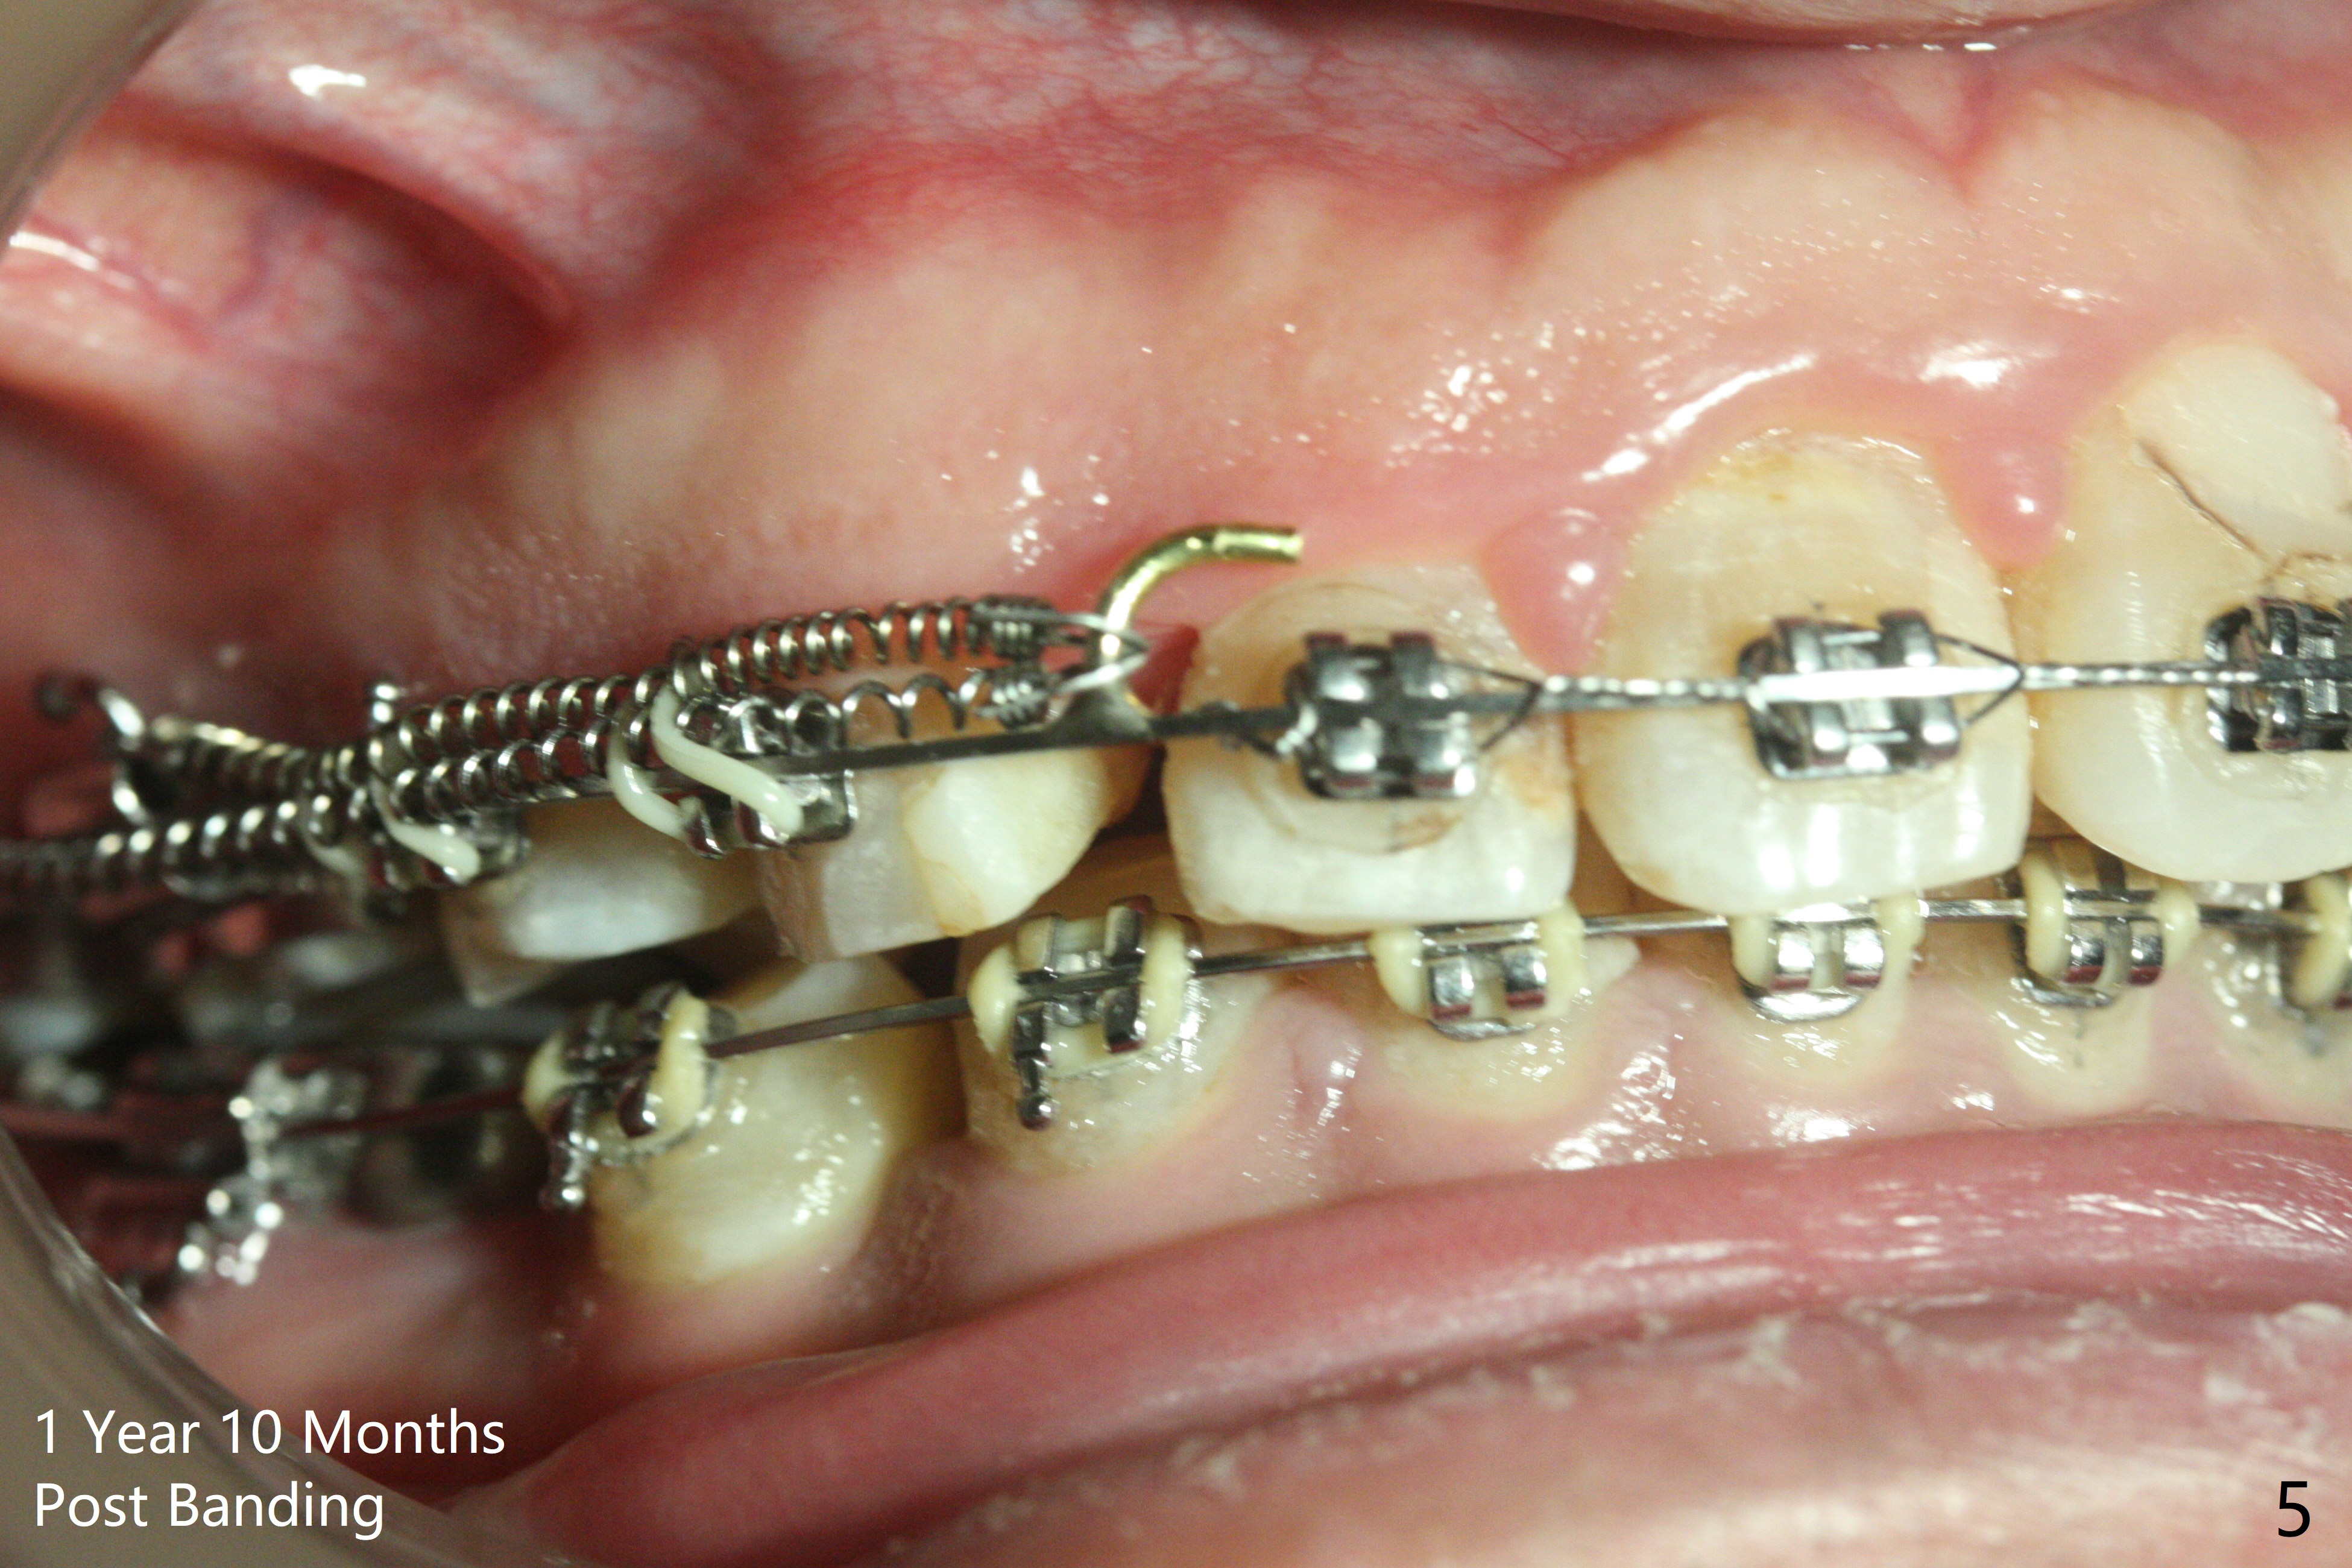

One year 4 months post banding (M) with 16x16 wires, UR3 is being distalized using UR7 as anchor (Fig.1), while the upper dental midline matches the facial one (Fig.2). The anterior overjet remains large (Fig.3). When UR3 is fully distalized, place posted wire to distalize U2-2 together. U2-2 distalization seems to be slow with one 16 mm closed coil spring each side (between 7 and post) 1 year 10 months post banding. Since the upper anterior PA shows mild root resorption at UR2 (Fig.4), a 14 mm closed coil spring is added each side (between 6 and post, Fig.5,6). LR6 has pain 2 years 2 months post banding (Fig.7). Debridement confirms non-salvageability; a 5x11.5 mm implant will be near the mesial root (Fig.8). Power chains for a month leads to closure of the gap between 3 and 4 (Fig.8-11). The space between 4 and 7 is 15 mm. A 12 mm 1st molar crown will be made, while the remaining 3 mm space will be closed by mesialization of 7 using 2 power posts mesial and distal to 6 and 7. Draw 2 tubes of blood. Make an incision to expose the mesial crest of 6.